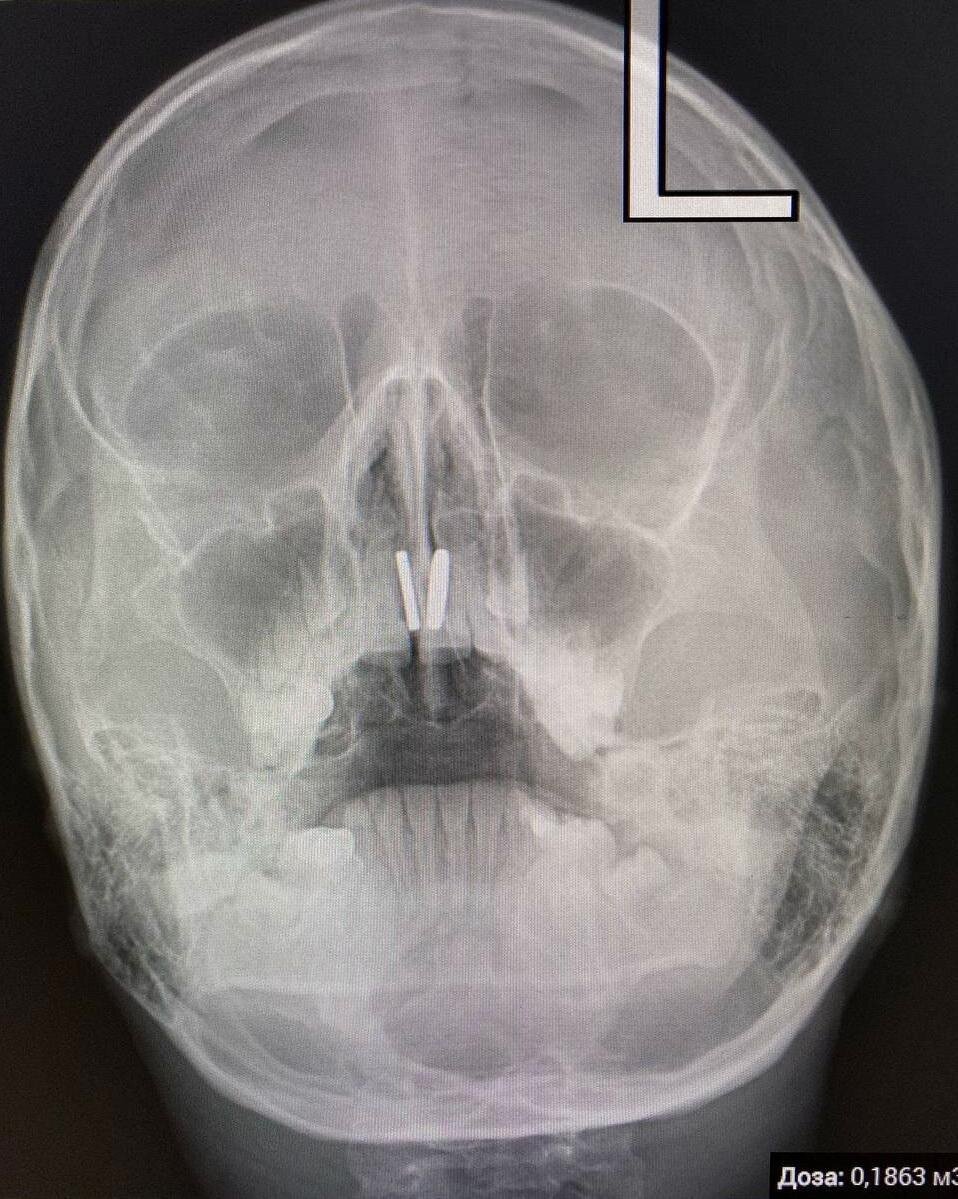

«С целью обследования сразу же была выполнена цифровая рентгенография. Ее огромный плюс в том, что помимо высокого качества снимка, она дает минимум лучевой нагрузки на пациента, - рассказывает дежуривший в тот день заведующий первым хирургическим отделением Артем Александрович Косов. - На снимке четко видна «магнитная клипса». Методом прямой риноскопии оба магнитика извлечены, пациентка и ее папа успокоены».

На все ушло не более получаса. И папа с дочерью, прихватив трофеи с собой, отправились домой. Все обошлось. Но если бы родители пытались извлечь инородные тела самостоятельно, или девочка рассказала бы им о случившемся казусе позднее, могли быть последствия. Как минимум, повреждение перегородки или ее прободение.